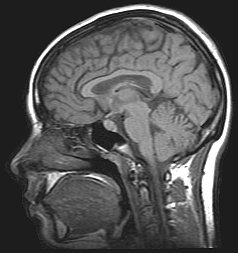

| Para a HII ser diagnosticada, escaneamentos de cérebro (como a ressonância magnética) devem ser realizados para garantir de que não há nenhuma causa subjacente para a pressão intracraniana aumentada | |

Para o diagnóstico é utilizado exames de imagem como a tomografia computadorizada, a ressonância magnética e Perimetria do Movimento para excluir a presença de tumores. Também é realizada punção lombar para manometria e exame do líquido cefalorraquidiano (LCR).